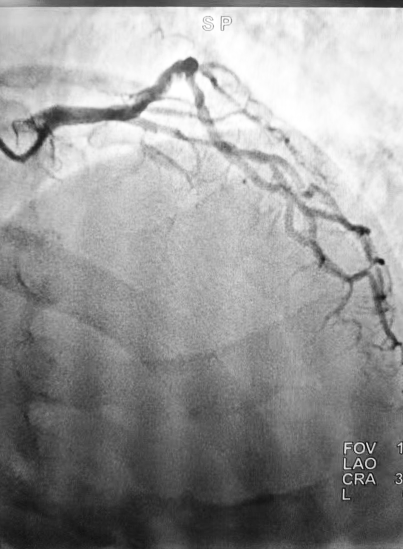

术中冠脉造影结果显示,梁大叔冠状动脉呈右冠优势型,左前降支近段以下完全闭塞,血流TIMI 0级(无血流灌注),左回旋支近段偏心性狭窄60%,右冠状动脉近中段弥漫性狭窄30-60%,后降支近中段狭窄85%,病情远比预想更为严峻。

(▲治疗前)